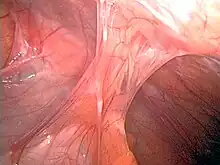

Adhesions formed following appendectomy |

Adhesions are fibrous bands that form between tissues and organs,[1] often as a result of injury during surgery. They may be thought of as internal scar tissue that connects tissues not normally connected.